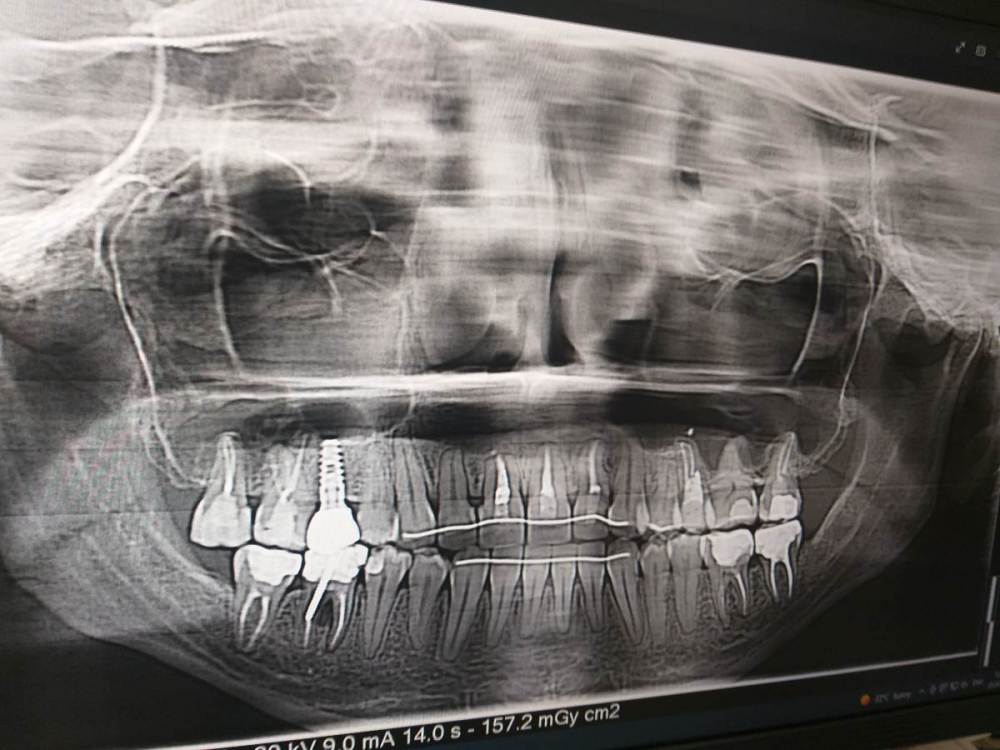

Ирина Артемьева Опубликовано 30 августа, 2022 Поделиться Опубликовано 30 августа, 2022 Здравствуйте! 2 года назад мне лечили 4 и 5 зуб слева наверху: на 4 зубе просто поставили пломбу, на 5 удалили нерв. Впоследствии оказалось что в 5 зубе мне сделали перфорацию. Далее этот зуб мне перелечил другой врач, боли притихли, но иногда зуб поднывал. На данный момент то есть 2 года спустя зуб начал беспокоить сильнее. Днем болит терпимо, а ночью мешает спать, приходится пить обезболивающие. С этими жалобами я пошла к стоматологу, который мне сказал что болеть может не 5, а 4 зуб и посоветовал удалить нерв в 4 зубе. Но я сомневаюсь, т.к. по моим ощущениям болит именно 5 зуб плюс боль отдает в ухо, в голову, также болит лицо около верхней челюсти. Что делать с 5 зубом- удалять или нет? И есть ли смысл удалять нерв в 4 зубе? Жду ваших ответов, т.к. очень устала от этой боли. Снимок какой есть прилагаю Ссылка на комментарий

Irouil Опубликовано 30 августа, 2022 Поделиться Опубликовано 30 августа, 2022 Нос слева не заложен? Могут болеть и 4-й, и 6-й зубы, надо их проверить на витальность. Если оба "живы", скорее всего это левосторонний гайморит от 5-го зуба, нужно делать КТ с захватом около носовых пазух Ссылка на комментарий

Doc Опубликовано 31 августа, 2022 Поделиться Опубликовано 31 августа, 2022 Заодно пора подумать о ситуации с 46 зубом (шестерка справа внизу). 1 Ссылка на комментарий